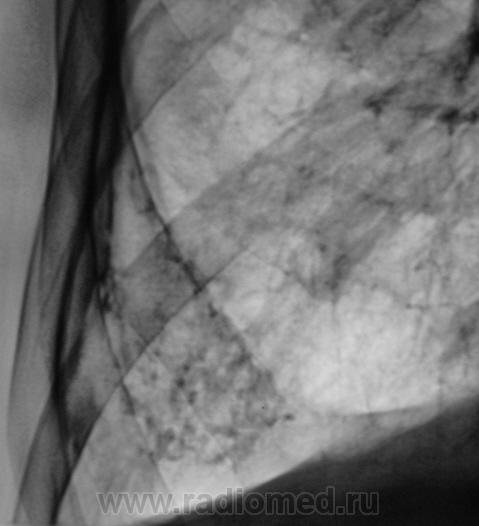

Болел, давно снят с учета. Клиническое излечение. Рецидив?

Рентгенограмма.

Я не очень хорошо разбираюсь в линейных томограмаах, но мне кажется что есть полости с обеих сторон, а это - показатель активности процесса.

Для доствоерности бы сделал КТ - если есть полости деструкции или "дерево-в -почках" - определенно активный процесс. (даже если не получено БК в мокроте). Можно тогда будет прицельно дать зону  с какой брать ПВБ.

На мой взгляд, полости есть.